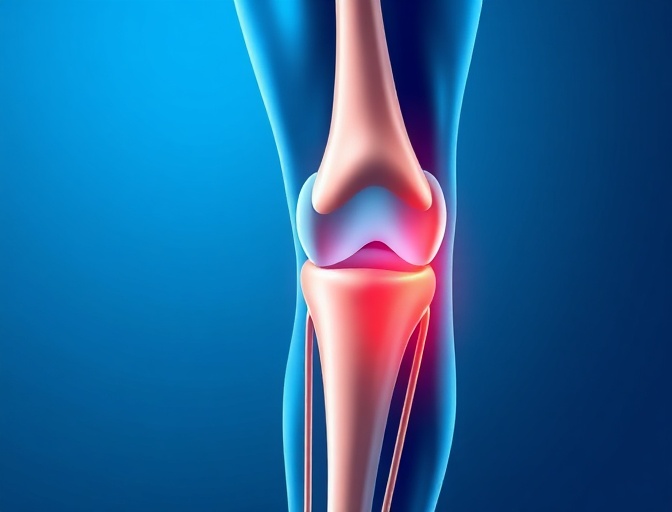

Knee Replacement

State-of-the-art total and partial knee replacement procedures that restore mobility and eliminate pain using the latest implant technology.

Knee Replacement Outcomes

Our knee replacement patients experience significant improvement in pain relief and functional ability, with 95% reporting excellent or good results.

"After suffering from knee pain for years, Dr. Mitchell performed my total knee replacement. The difference is remarkable - I'm back to hiking and playing with my grandchildren pain-free. The entire process was smooth and his team was incredibly supportive."

Robert Anderson

Total Knee Replacement